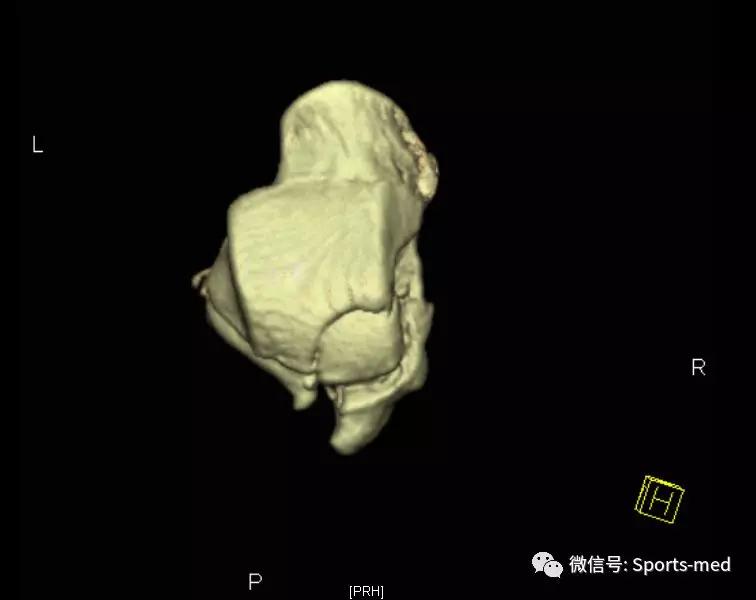

当地两家医院给出了两种方向的建议:切开手术治疗、打石膏保守治疗,同时主张手术的医生还告知了各种可能的风险,比如距骨坏死、移位、不愈合、皮肤坏死等,而主张保守治疗的医生之所以建议保守是因为:坏死机率和发生创伤性关节炎几率很高,做和不做差不太多,看到这个片子的第一眼,我并没有马上给我的治疗建议,而是先让他做一个踝关节三维ct,判断骨折情况,三维ct结果要比我们想象中的好很多,骨折块位置还好。

经过与患者的沟通和交流,我们提出了如下治疗方案:内镜监视下骨折闭合复位空心钉内固定,选择这个治疗的原因有:患者还很年轻,运动欲望强烈;关节面不平整,踝关节以及距下关节均有累积;骨折部位靠近后方,关节镜比较容易处理。

我们采用常规的后内、后外入路,清理关节内的淤血,并探查骨折情况,与ct显示基本一致,骨折形成三部分,并累积了关节面